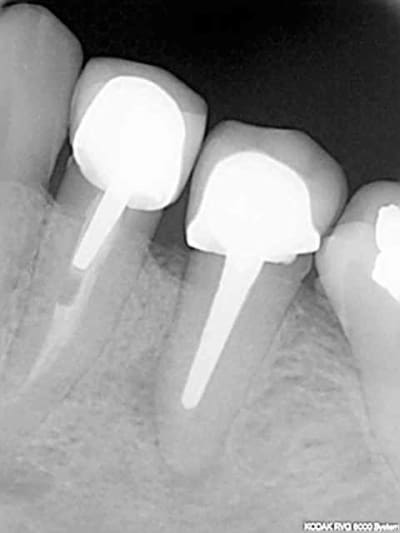

Plus sérieusement sur le premier cas le foret en place est le terminal de 12x3,5, je le trouve pas si mal l'axe 3d, mais j'ai un peu forcé sur le biomat

pour l'autre cas, je suis aussi dans l'axe,j'avais décalé le deuxieme forage en palatin pour faire une expansion

vesti, puis j'ai choisi la facilité

Olivier et les autres, pouvez-vous détailler ce qui dans le positionnement 3D a amené un tel échec esthétique?

Je dirai un axe vestibulo-palatin trop incliné en vestibulaire, mais est-ce la seule cause?

Désolé, mais le résultat des couronnes secteurs 2 sur implants n'est pas tès intéressant...et je crois que l'axe est en cause...

est ce que c'est mieux pour l'axe?

un peu d'humour ne "nuit" pas

Par contre la remarque de Noah m'a interpellé, je suis peut être par habitude devenu trop minimaliste, il faut savoir se remettre en cause

mardi pour la centrale je prend des photos du moignon tranvissé puis de la céram et on en discute

Pour arno et la patiente qui me vaut ces critiques, pour un autre axe il fallait simplement une greffe osseuse+ une gingivale et une expansion